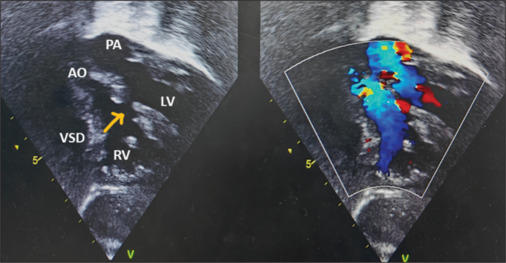

一种罕见但具有历史意义的大动脉转位(TGA)变异于1971年首次被发现。后向右的主动脉、不发达的主动脉下圆锥和发育良好的肺下圆锥是本病的特征。大血管的关系类似于正常相关的大动脉,肺动脉位于前面,主动脉位于后面。本报告描述了一例TGA变异伴室间隔缺损的患者,该患者接受了成功的动脉转换手术。尽管大动脉的位置不寻常,冠状动脉转移和肺动脉吻合是有效的。尽管已发表的文献建议在这种解剖结构中不采用LeCompte手法,但我们在该病例中采用了前后环状冠状动脉,以保护近端冠状动脉免受过度拉伸。

A rare but historically significant variant of transposition of the great arteries (TGA) was first identified in 1971. A posterior and rightward-positioned aorta, an underdeveloped subaortic conus, and a well-developed subpulmonary conus characterize this entity. The relationship of the great vessels mimics that of normally related great arteries, with the pulmonary artery positioned anteriorly and the aorta located posteriorly. This report describes a patient with such a variant of TGA, associated with a ventricular septal defect, who underwent a successful arterial switch operation. Despite the unusual positioning of the great arteries, coronary artery transfer and pulmonary artery anastomosis were effectively performed. Although published literature advises against performing LeCompte's maneuver in such anatomy, we performed the maneuver in this case with anterior and posterior looping coronaries to protect the proximal coronary arteries from excessive stretch.